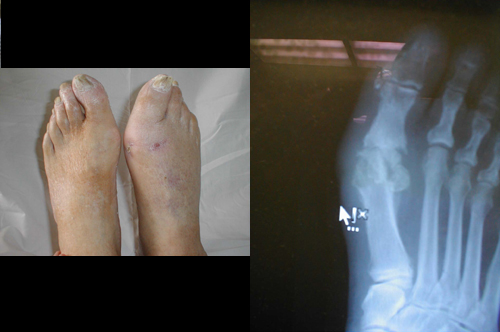

التهاب العطم و النقي ( المزمن )

التهاب العظم و النقي المزمن في المنطقة المشطية للإصبع الكبرى أدى إلى إحداث توذم دائم في تلك المنطقة . وعن طريق الأشعة السينية يمكن مشاهدة التهدم العظمي في هذه المنطقة .